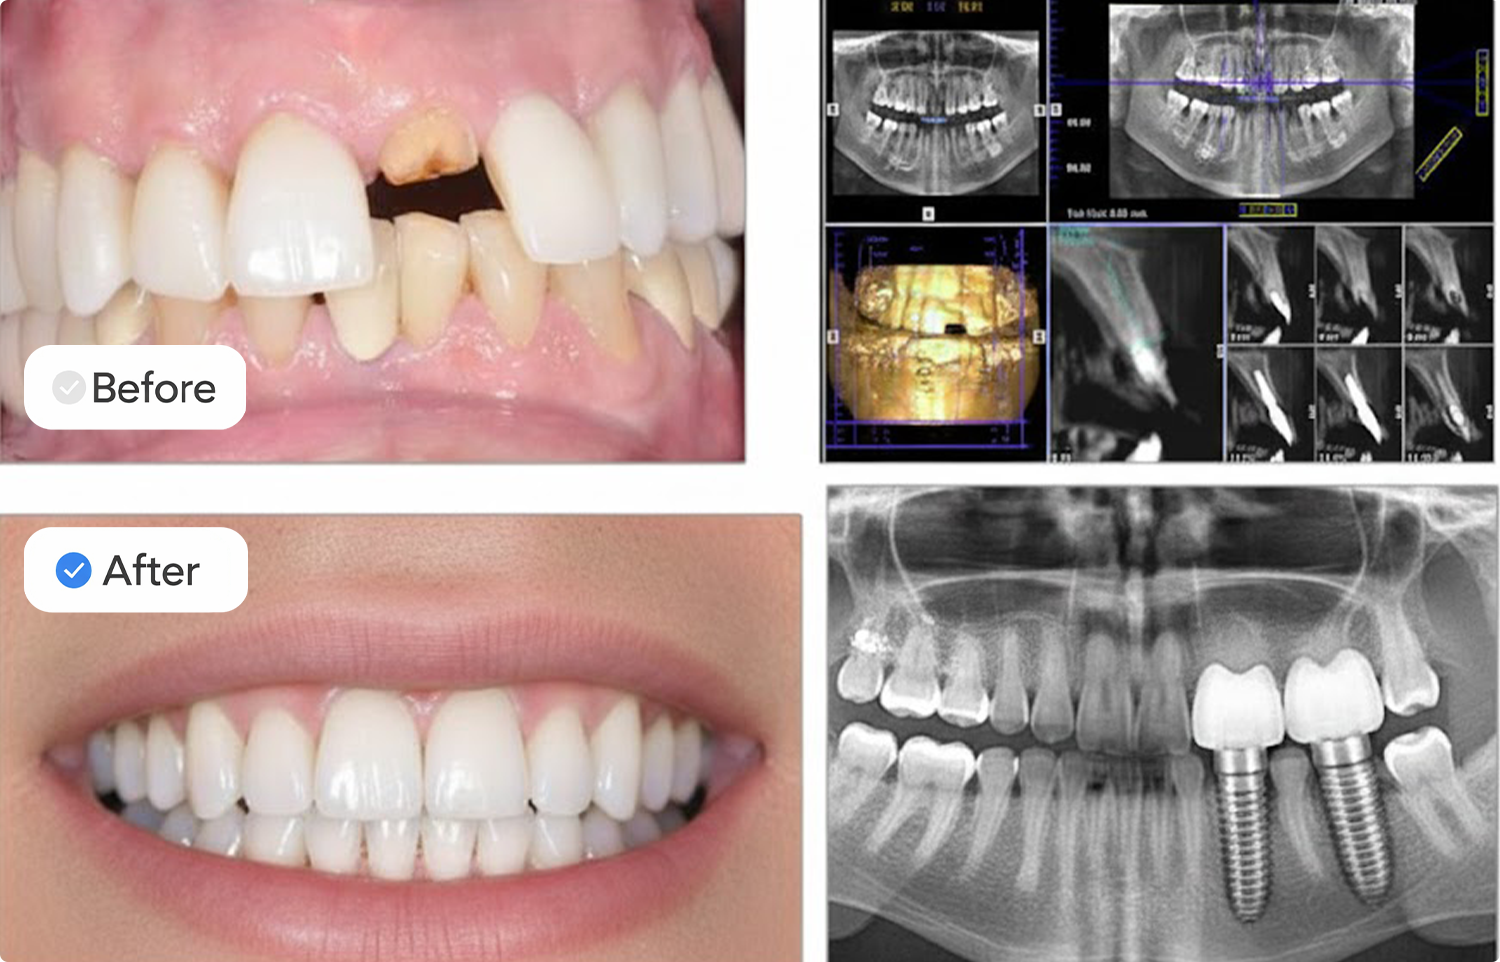

Emergency Dentistry Before & After

These examples show real before and after improvements from emergency dental cases treated at our clinic. Each case highlights fast repairs, reduced pain, and restored function through urgent dental repair and same-day treatment.

These real patient outcomes show how rapid restoration and immediate care can create visible improvement and fast recovery.